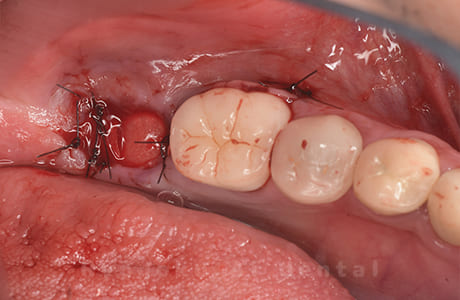

Case07

- 原因

- 右下6番歯根破折

-

- 治療内容

- インプラント治療

- 治療費用

- 約600,000円

右下の腫れが治らないとの事でご来院された患者様です。歯が割れていたため、抜歯を行い、骨に代わるお薬を入れ、インプラントを埋入致しました。経過良好で大変満足していただけました。

<リスク・副作用>

治療後、痛みや違和感、出血、腫れなどが出る事があります。喫煙者、糖尿病などの方の場合、歯が生着しない場合があります。